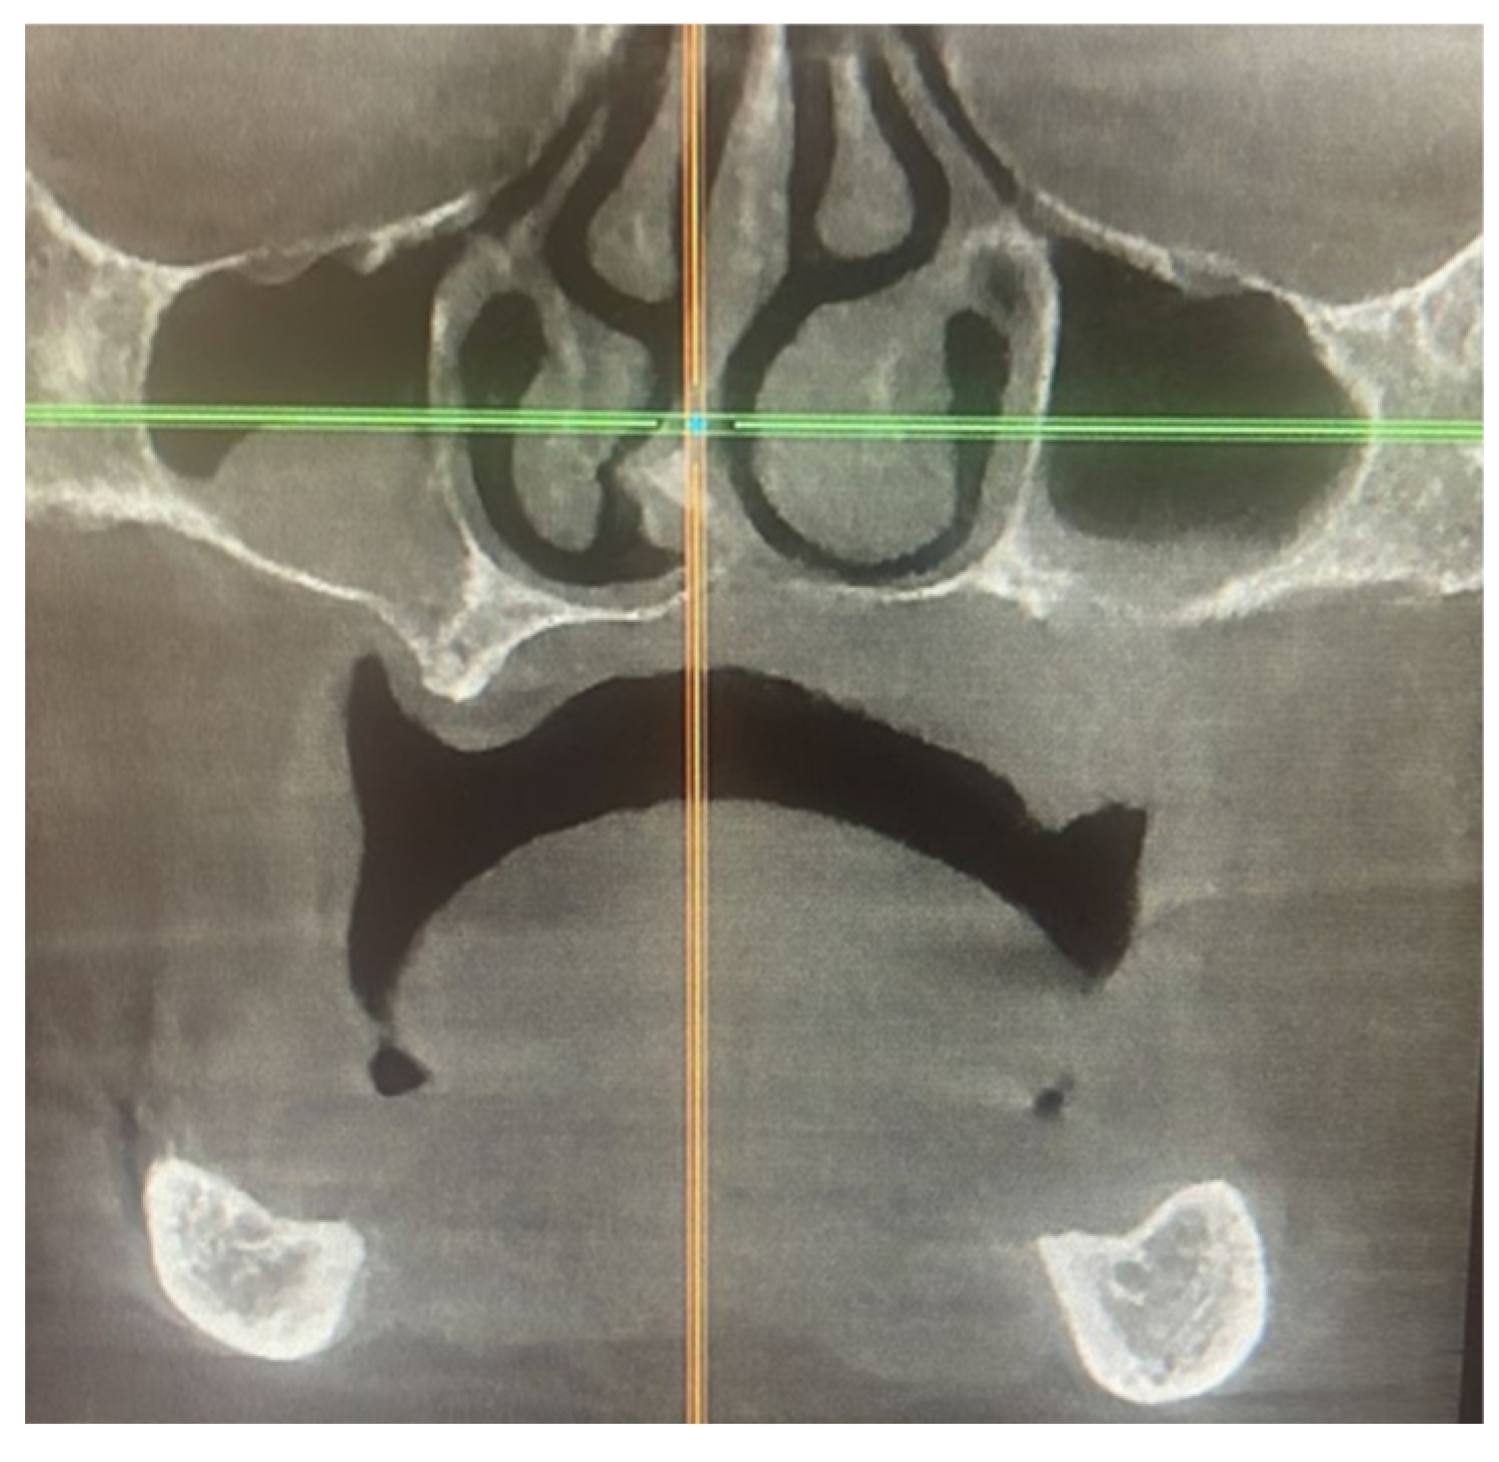

The computed tomography (CT) scan of the facial bones, with a focus on the hard palate, showed an increase in the left palatal mucosa thickness, cortical irregularity, and osteolysis of the inferior border of the maxillary sinus (Figure 2).

Figure 2. Computed tomography (CT) scan coronal view showing an increase in the left palatal mucosa thickness, cortical irregularity, and osteolysis of the inferior border of the maxillary sinus.